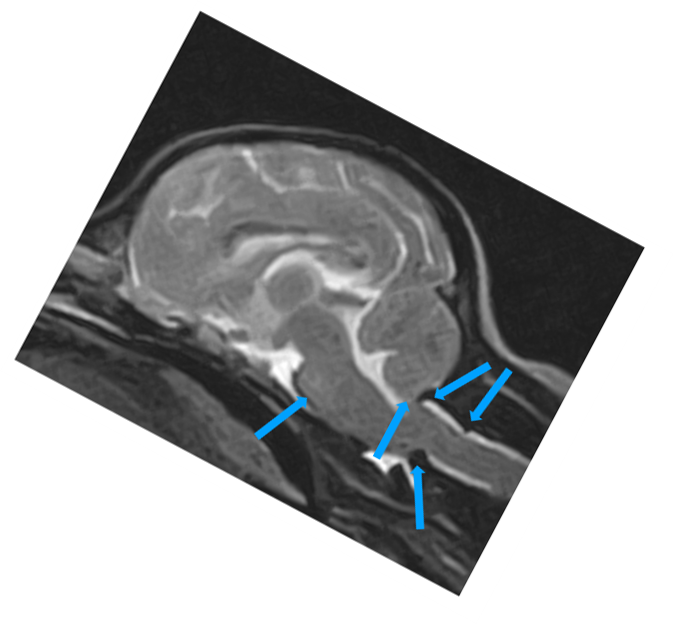

• malformacje Chiariego

• wady złącza czaszkowo mózgowego